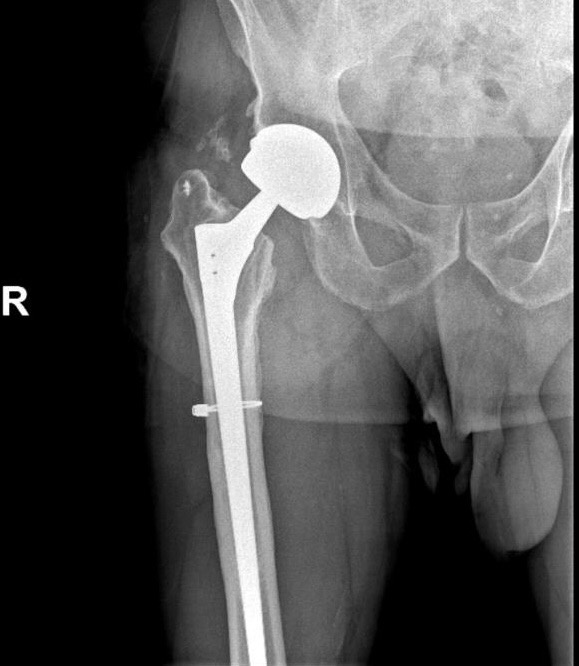

Активности после эндопротезирования тазобедренного сустава - одна из любимых моих тем. На фото выше - мой пациент, о котором я уже писал неоднократно. Самый, на мой взгляд, уникальный триатлонист, который в 62 года НАЧАЛ заниматься триатлоном. В процессе тренировок сломал шейку бедра, эндопротезирование; сломал бедро вокруг ножки протеза - ревизионное эндопротезирование. Сейчас ему 74. Вчера получаю сообщение от товарища-реабилитолога: «9 числа Леонид, катаясь на горных лыжах в Италии по ледяному склону, упал, и врезался правым боком в деревянное ограждение. Вывихнул фалангу большого пальца кисти, сломал нижние рёбра, ударился бедром; онивесь ушибленный, ушиб всего Леонида… (дальше вопросы)… Бедро у него болит в паху, когда ходит медленно, акогда он подбегивает (со сломанными рёбрами!!!), или когда занимается на эллипсе - не болит….. (детали)…. В целом у Леонида вообще всё отлично - он опять стал бегать, со спортивной ходьбы перешел на бег, и уже 20 км он бегал, в ближайшее время по

Активности после эндопротезирования тазобедренного сустава - одна из любимых моих тем. На фото выше - мой пациент, о котором я уже писал неоднократно. Самый, на мой взгляд, уникальный триатлонист, который в 62 года НАЧАЛ заниматься триатлоном. В процессе тренировок сломал шейку бедра, эндопротезирование; сломал бедро вокруг ножки протеза - ревизионное эндопротезирование. Сейчас ему 74.

Чтобы было понятно - стоит вот такой протез: